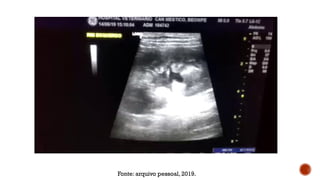

Fonte: arquivo pessoal, 2019.